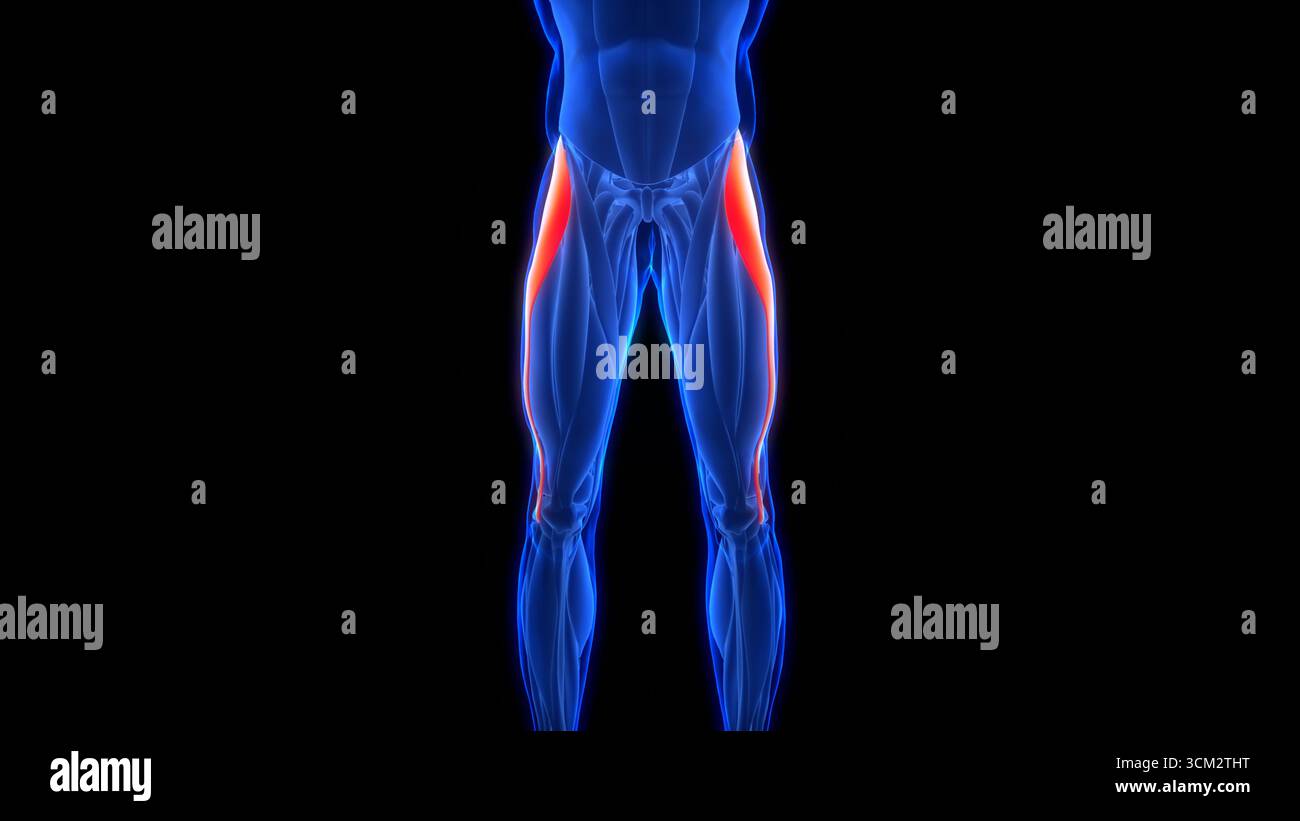

Human Muscular System Leg Muscles Tensor Fasciae Latae Muscles Anatomy Stock Photohttps://www.alamy.com/image-license-details/?v=1https://www.alamy.com/human-muscular-system-leg-muscles-tensor-fasciae-latae-muscles-anatomy-image700771049.html

Human Muscular System Leg Muscles Tensor Fasciae Latae Muscles Anatomy Stock Photohttps://www.alamy.com/image-license-details/?v=1https://www.alamy.com/human-muscular-system-leg-muscles-tensor-fasciae-latae-muscles-anatomy-image700771049.htmlRF3CM2THD–Human Muscular System Leg Muscles Tensor Fasciae Latae Muscles Anatomy

Human Muscular System Leg Muscles Tensor Fasciae Latae Muscles Anatomy Stock Photohttps://www.alamy.com/image-license-details/?v=1https://www.alamy.com/human-muscular-system-leg-muscles-tensor-fasciae-latae-muscles-anatomy-image700771060.html

Human Muscular System Leg Muscles Tensor Fasciae Latae Muscles Anatomy Stock Photohttps://www.alamy.com/image-license-details/?v=1https://www.alamy.com/human-muscular-system-leg-muscles-tensor-fasciae-latae-muscles-anatomy-image700771060.htmlRF3CM2THT–Human Muscular System Leg Muscles Tensor Fasciae Latae Muscles Anatomy